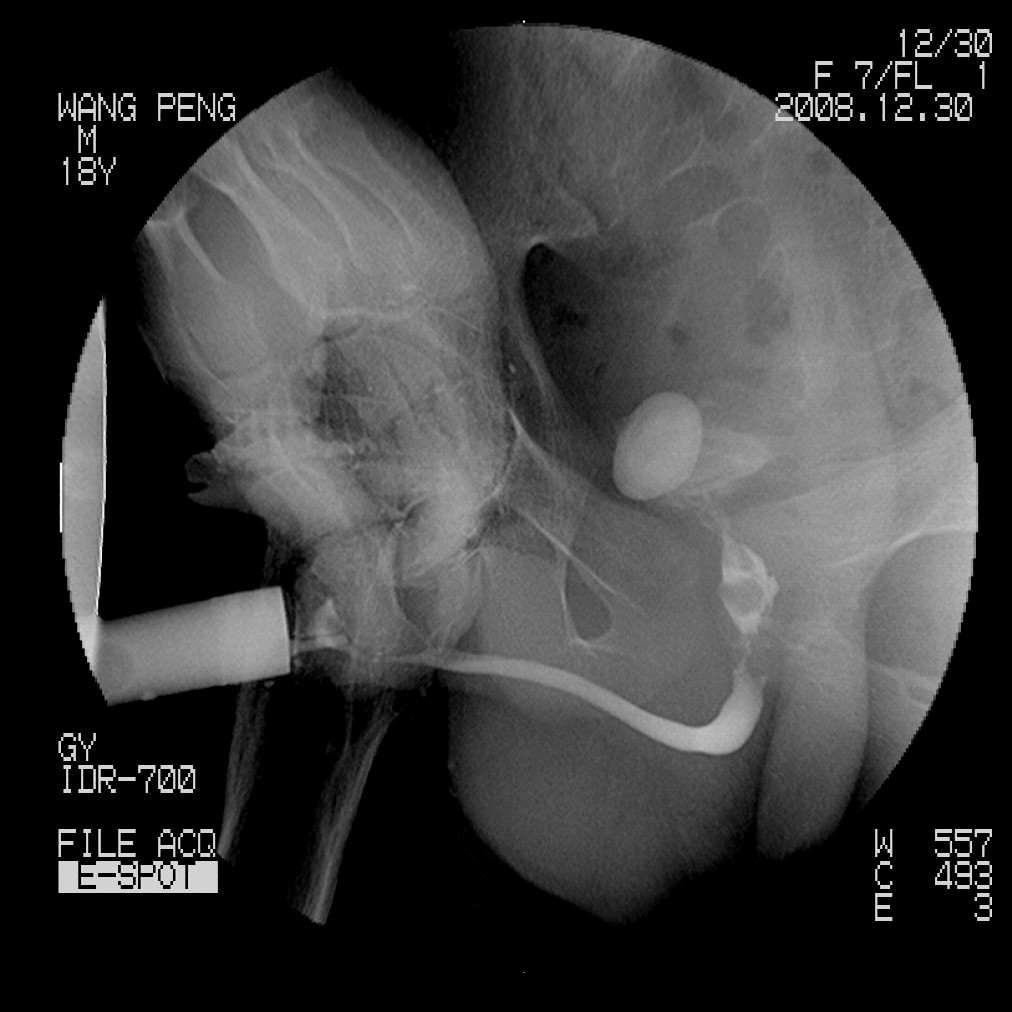

标题: X6910:经典的膀胱及尿道多发结石 [打印本页]

标题: X6910:经典的膀胱及尿道多发结石

患者,男,18岁,尿流不畅数月。

膀胱及后尿道多发结石,谢楼主分享

膀胱及尿道多发结石。

膀胱及后尿道多发结石,谢谢分享---------------------------